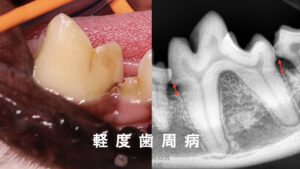

続いて、下の写真を見てみましょう。

先程の子の歯並びと違って、目印の歯の間には上の歯が1本、下の歯が2本しか生えていません。

つまり、上の歯も下の歯も2本ずつ少ないのです。

ここで、足りない歯がもともと無い欠損歯なのか、埋まっている埋伏歯なのかがとても重要になります。

欠損歯と埋伏歯は見た目で見分けることはできないため、レントゲン写真で確認します。